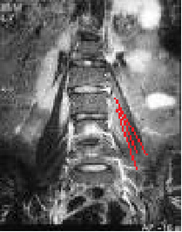

Det gemensamma för uppkomsten av ryggbesvär är en felaktig rörlighet mellan två eller flera kotor. Smärtan kan komma från disken eller från de små kotlederna. Dessa kan i sin tur vara skadade av olika anledningar som; -diskbråck, -kotglidning, -diskdegeneration eller resttillstånd efter en kotfraktur.